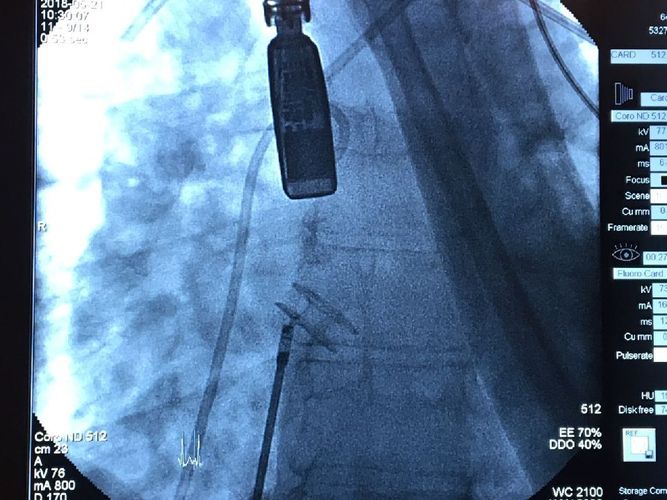

The first cardiological surgery in Poland – the implantation of the atrial flow regulator (AFR) was held on May 21, 2018, at the University Clinical Centre (UCC). It is the result of cooperation between the MUG’s Department of Paediatric Cardiology and Congenital Heart Defects and the Clinical Cardiology Centre of the UCC.

The 28-year-old patient underwent correction of complex congenital heart disease in early childhood and developed severe pulmonary hypertension. Alicja Dąbrowska-Kugacka M.D. Ph.D. qualified the patient for the procedure and the surgery was carried out by prof. Robert Sabiniewicz M.D. Ph.D. and Dariusz Ciećwierz M.D. Ph.D., as well as Joanna Kwiatkowska M.D. Ph.D. and prof. Marcin Fijałkowski M.D. Ph.D.